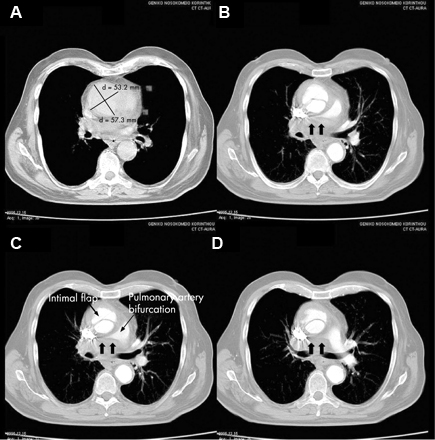

CT of a 71-year-old man showing type II dissecting aneurysm of the ascending aorta. Haematoma around the proximal segment of the ascending aorta (panels A-D) compressed the right pulmonary artery, almost occluding its patency and limiting the perfusion of the reciprocal lung

Stougiannos PN, Mytas DZ, Pyrgakis VN. The changing faces of aortic dissection: an unusual presentation mimicking pulmonary embolism. BMJ Case Reports 2009; doi:10.1136/bcr.2006.104414